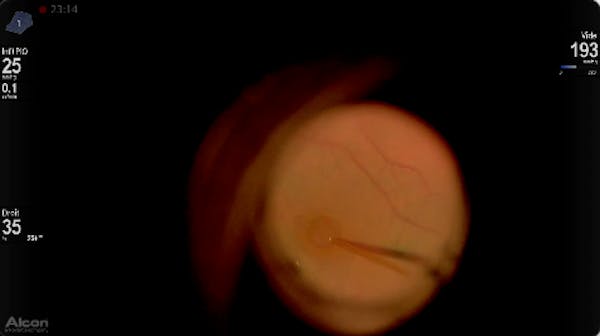

Slawomir Cisiecki, MD

Andre Gomes, MD